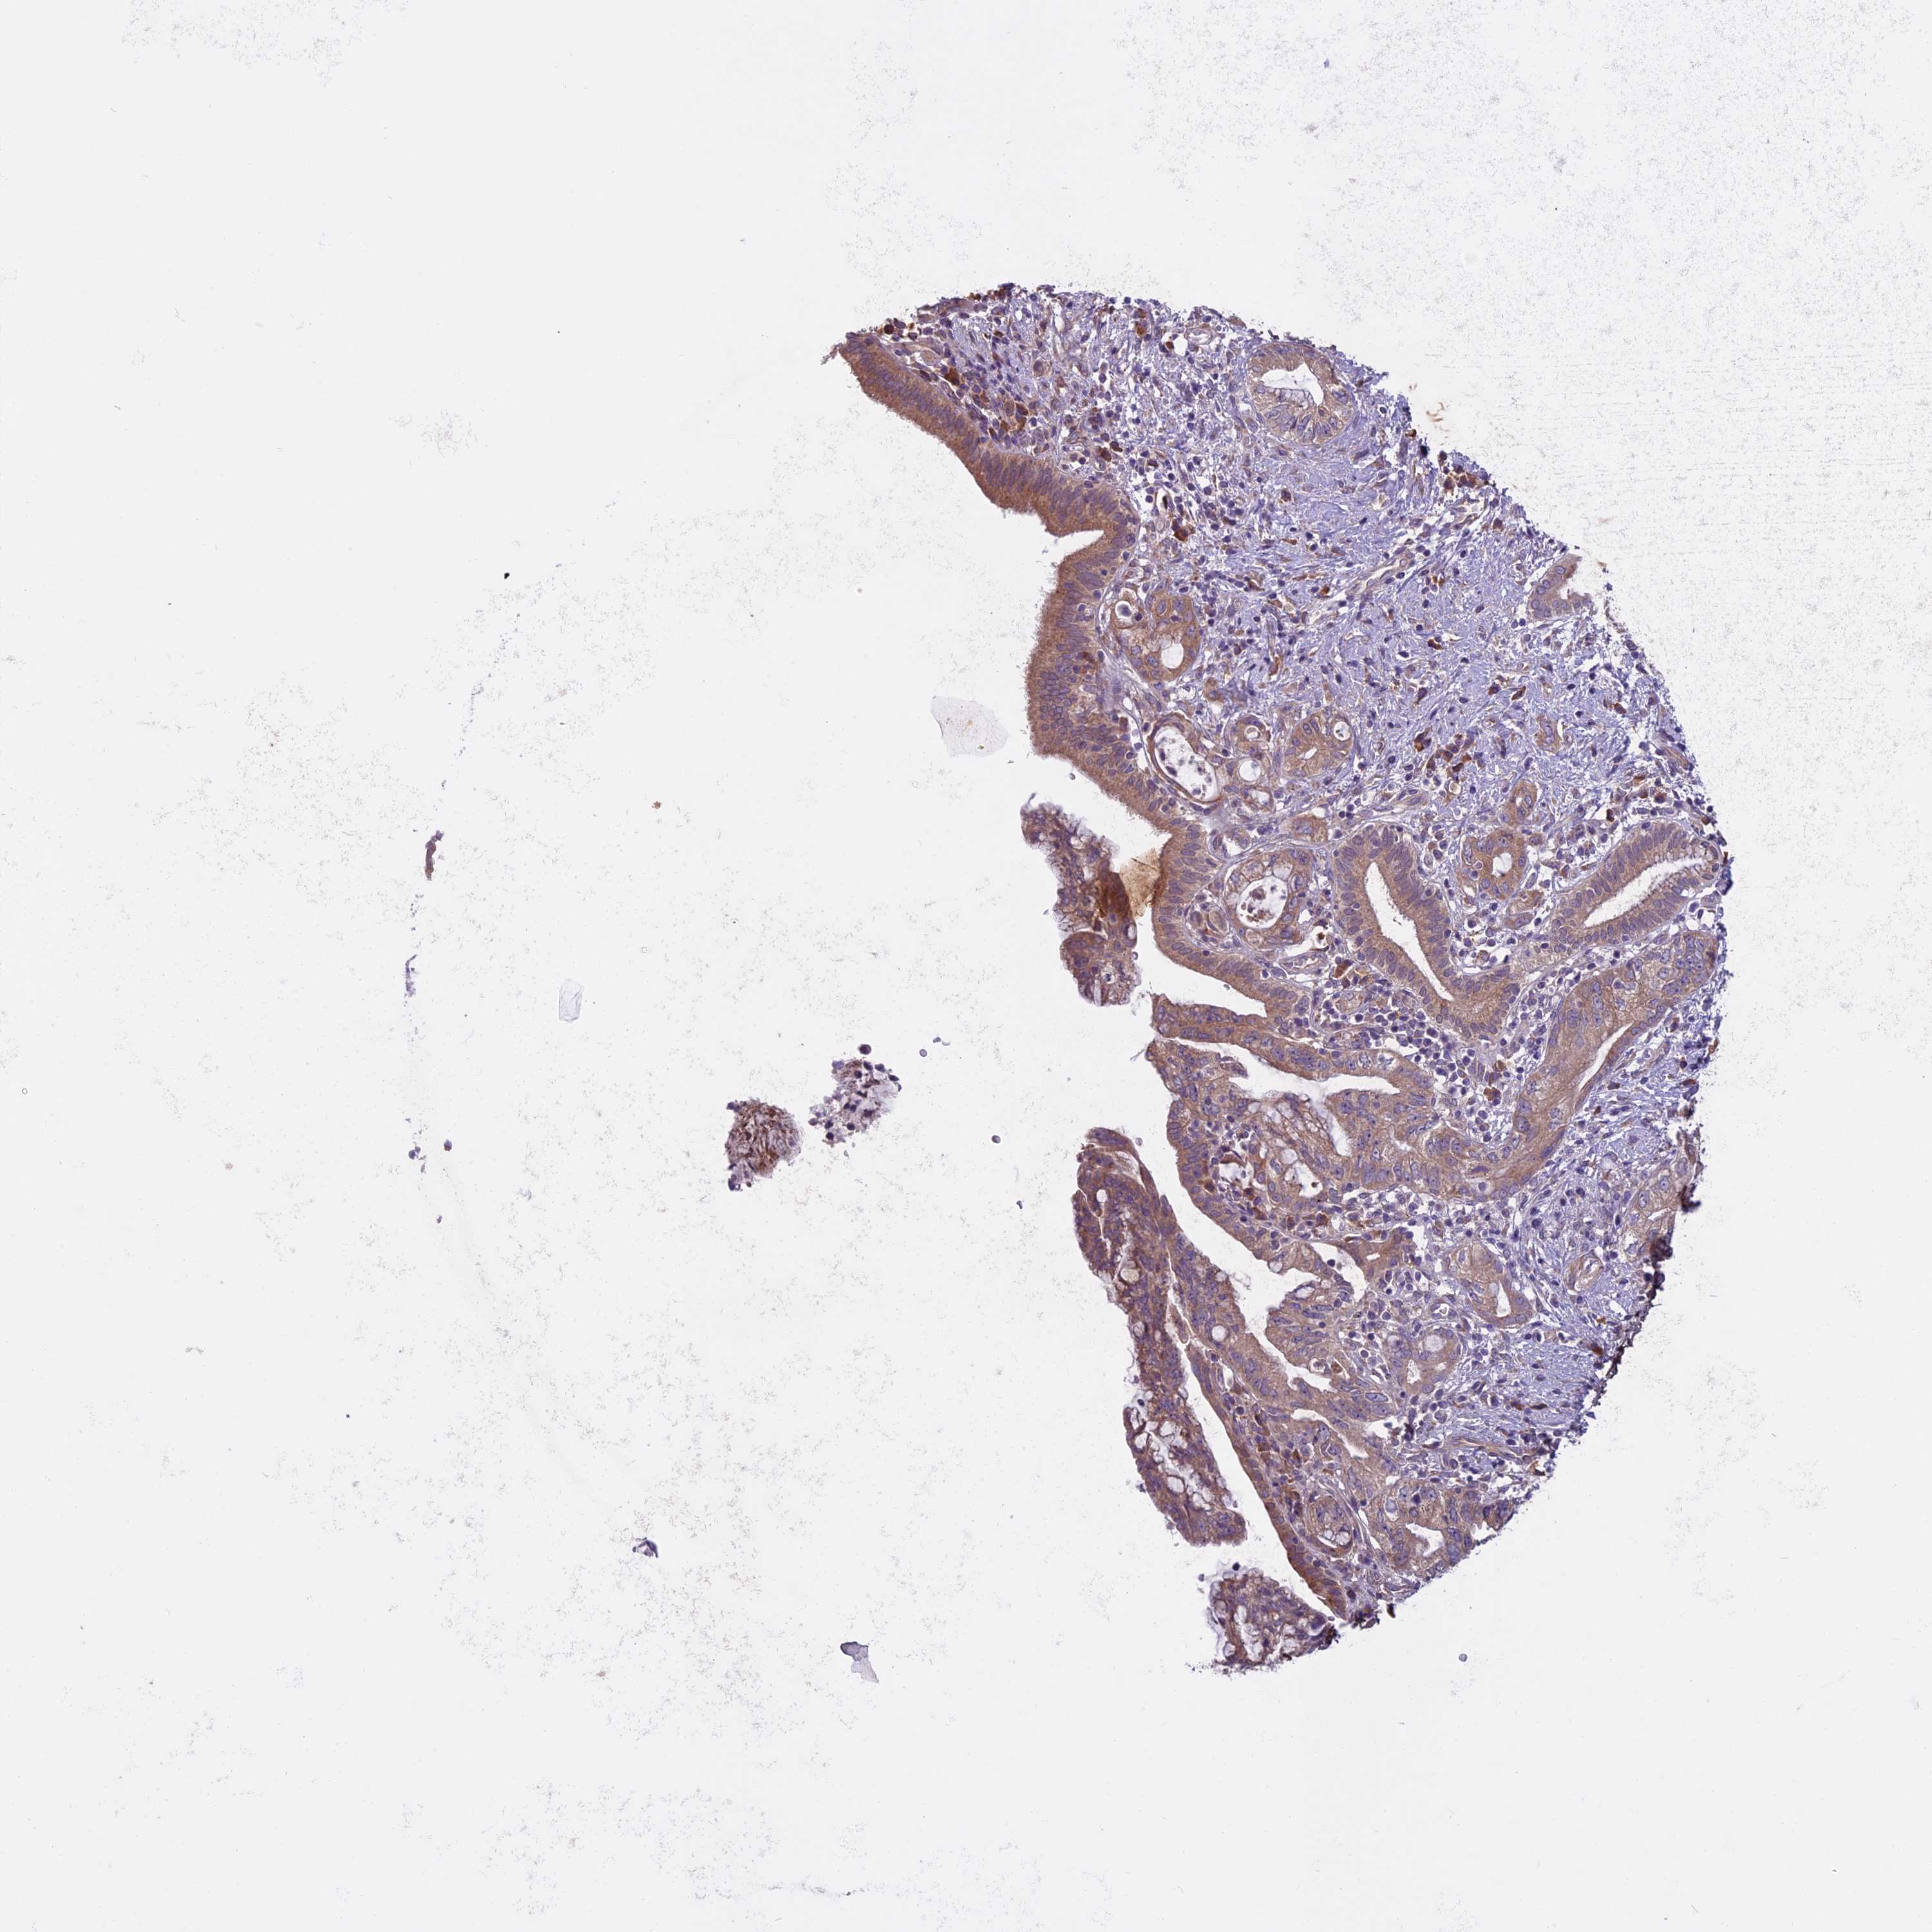

PANCREATIC CANCER - Protein expressioni

A mouse-over function shows sample information and annotation data. Click on an image to view it in a full screen mode. Samples can be filtered based on level of antibody staining by selecting one or several of the following categories: high, medium, low and not detected. The assay and annotation is described here.

Note that samples used for immunohistochemistry by the Human Protein Atlas do not correspond to samples in the TCGA dataset.

Antibody stainingi

Antibody staining in the annotated cell types in the current human tissue is reported as not detected, low, medium, or high, based on conventional immunohistochemistry profiling in selected tissues. This score is based on the combination of the staining intensity and fraction of stained cells.

Each image is clickable and will lead to virtual microscopy that enables deeper exploration of all samples and also displays staining intensity scores, fraction scores and subcellular localization as well as patient and tissue information for each sample.

Antibody HPA042003

Staining

High

Medium

Low

Not detected

Intensity

Strong

Moderate

Weak

Negative

Quantity

>75%

75%-25%

<25%

None

Location

Nuclear

Cytoplasmic/membranous

Cytoplasmic/membranous,nuclear

Adenocarcinoma, NOS